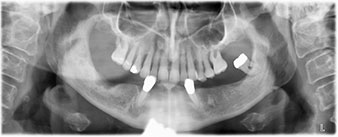

The 64-year-old patient presented with residual dentition of teeth 38, 33 and 43 and a clasp denture in the mandible (Fig. 1 and 2).

residual dentition

Fig. 1

Fig. 2

A three-dimensional cone beam computed tomography scan (CBCT, Planmeca) was performed to aid planning and minimize risks. This revealed that the quality and quantity of the available bone were sufficient for the surgery and immediate restoration using the Fast & Fixed method. Following the protocol for this concept, the implants are inserted at 35, 32, 42 and 45. Angling the distal implants by up to 45° shifts the emergence profile to posterior and generates a larger support polygon (Fig. 3).